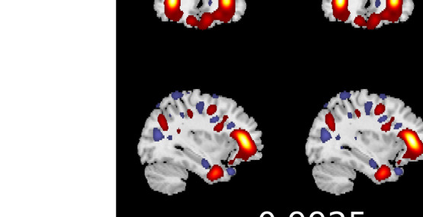

In the last two decades, unsupervised latent variable models---blind source separation (BSS) especially---have enjoyed a strong reputation for the interpretable features they produce. Seldom do these models combine the rich diversity of information available in multiple datasets. Multidatasets, on the other hand, yield joint solutions otherwise unavailable in isolation, with a potential for pivotal insights into complex systems. To take advantage of the complex multidimensional subspace structures that capture underlying modes of shared and unique variability across and within datasets, we present a direct, principled approach to multidataset combination. We design a new method called multidataset independent subspace analysis (MISA) that leverages joint information from multiple heterogeneous datasets in a flexible and synergistic fashion. Methodological innovations exploiting the Kotz distribution for subspace modeling in conjunction with a novel combinatorial optimization for evasion of local minima enable MISA to produce a robust generalization of independent component analysis (ICA), independent vector analysis (IVA), and independent subspace analysis (ISA) in a single unified model. We highlight the utility of MISA for multimodal information fusion, including sample-poor regimes and low signal-to-noise ratio scenarios, promoting novel applications in both unimodal and multimodal brain imaging data.